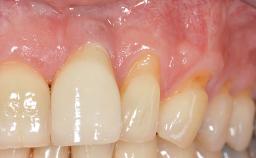

A 30-year-old woman was referred by her general dentist for evaluation of an esthetic complication related to previous implant treatment for congenitally missing maxillary lateral incisors. The patient’s chief complaint was the inadequate esthetic appearance of her smile. The case demonstrates the use of a combined approach to achieve optimal results. Two different flap designs - a tunnel technique and a coronally advanced flap - are employed based on the surgical objectives for the affected site.

Soft Tissue Grafting Yes